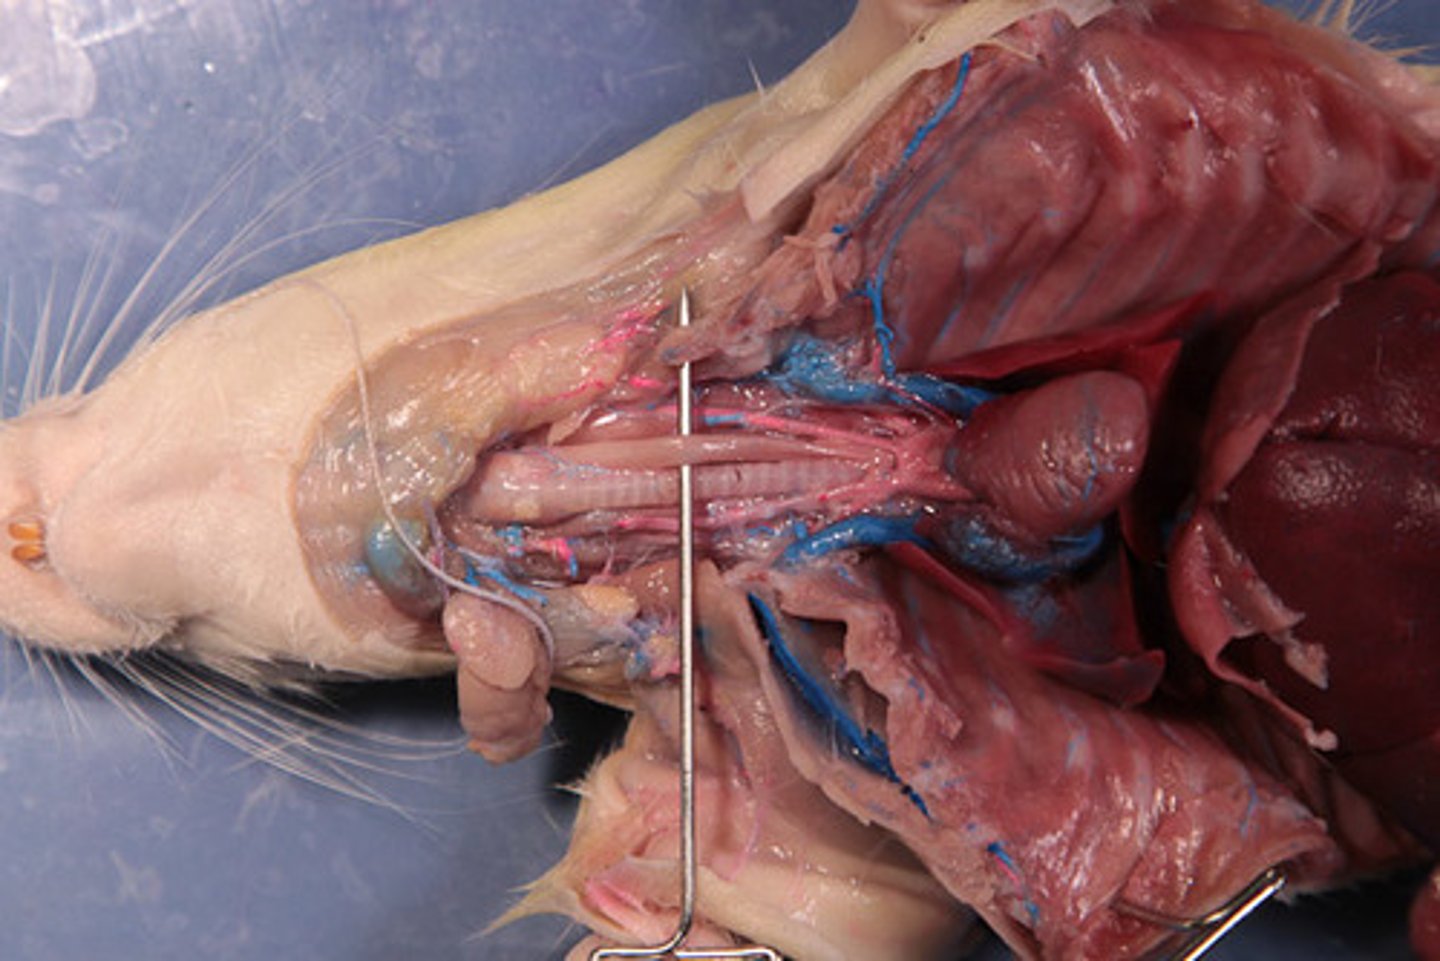

liver

pin

cystic duct

common hepatic duct

Gallbladder

portal vein

pancreas

organ

pancreatic duct

common bile duct

spleen

hepatopancreatic sphicter / duodenal papilla